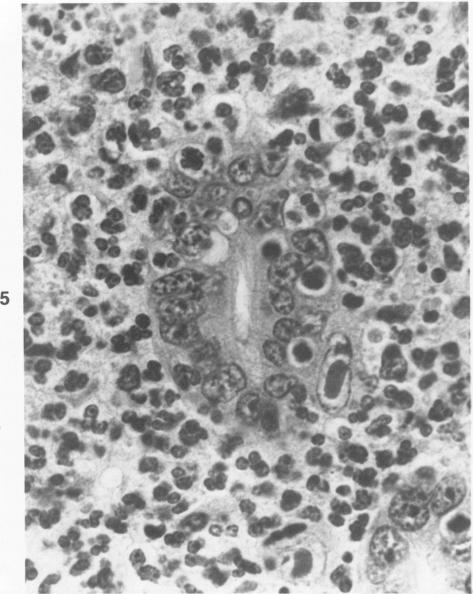

Rhesus monkeys experimentally infected with the lentivirus SIV/Delta become immunodeficient and often die of opportunistic infections. The most frequent of these is cytomegalovirus (CMV). The lesions due to reactivated CMV infection in 14 SIV-infected monkeys were reviewed. Changes due to CMV were observed in the brain, lung, lymph node, liver, spleen, small intestine, testicle, nerves, and arteries. Disseminated CMV infection in immunodeficient rhesus monkeys is a useful model for studying the pathogenesis, treatment, and prevention of similar infections in immunodeficient human beings.

实验感染慢病毒SIV/Delta的恒河猴会出现免疫缺陷,常死于机会性感染。其中最常见的是巨细胞病毒(CMV)。回顾了14只感染SIV的猴子因CMV感染再激活而出现的病变。在脑、肺、淋巴结、肝、脾、小肠、睾丸、神经和动脉中观察到了由CMV引起的变化。免疫缺陷恒河猴中的播散性CMV感染是研究免疫缺陷人类中类似感染的发病机制、治疗和预防的有用模型。